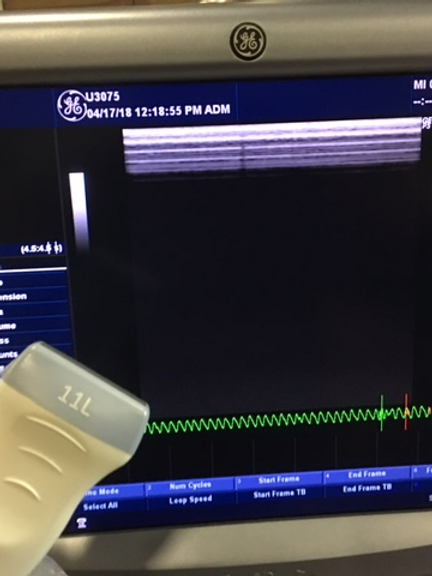

- Directional power Doppler imaging for detailed vascular assessments

- High pulse repetition rate for improved diagnostic accuracy